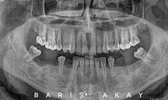

Dt. Barış Akay Dentist

Toothache

Dental caries

Tooth deficiency

Dental and periodontal diseases

Jaw cysts

Implant treatment